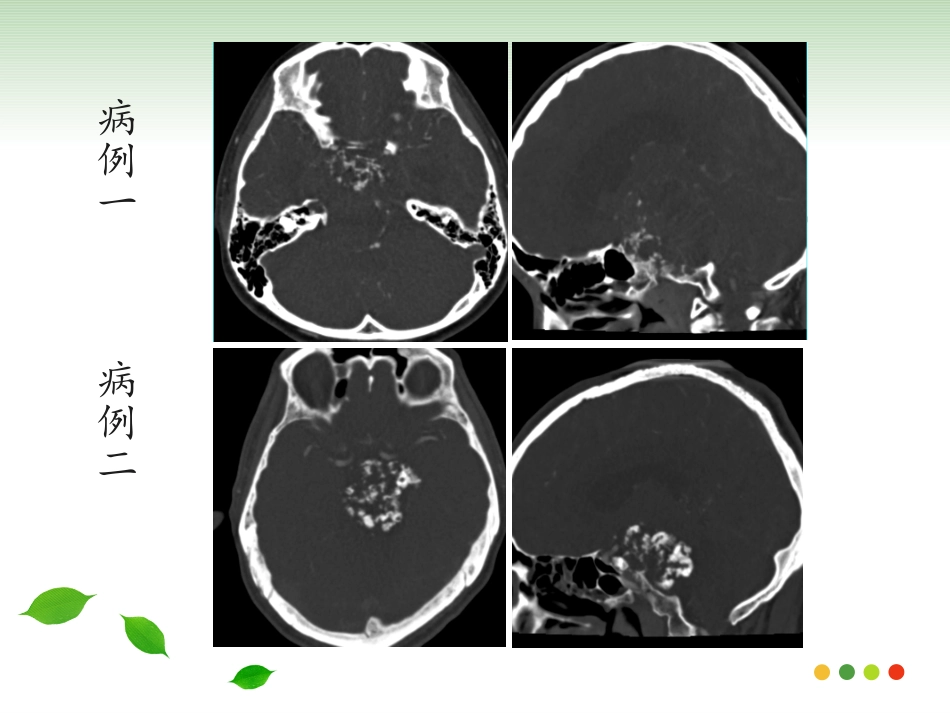

病例1:女,10岁,视物重影1月余病例2:男,47岁,视物重影2年余病例一病例二斜坡脊索瘤的影像诊断斜坡脊索瘤的影像诊断福建医科大学附属第一医院影像科2017级周晓芳发病机理发病机理•脊索是人体脊柱的原基,形成于胚胎期的第3周,上方由头盖骨的Rathke’s袋限制在蝶骨,向下和咽部相连,接着穿过齿状突和椎体中央•胚胎发育成为颅底的一部分和脊柱,残存的脊索组织可发展成为脊索瘤。概述概述•脊索瘤是一种比较少见的来源于脊索胚胎残余物的低度恶性肿瘤。•占颅内肿瘤的1%,占所有原发性骨肿瘤的4%•斜坡由枕骨基底部和蝶骨体共同组成,上界为鞍背,下界为枕骨大孔前缘,分上、中或下区。上区相当于蝶骨体,中区为蝶枕软骨结合处,下区为枕骨基底部,以中区最多见临床表现临床表现•可发生于任何年龄,成年人多见,30-40为高峰•男女比例2:1•生长缓慢,症状隐匿•最常见复视、颅神经麻痹及头痛;外展神经受累最常见,头痛通常在枕部或眶后位置病理表现病理表现•光镜下脊索瘤细胞胞浆丰富、内含黏液和大量空泡,也称液滴细胞;瘤细胞呈索条样分布,其间可见大量的黏液基质。•分为两个亚型:以液滴细胞为主、缺少软骨成分者为经典型;局灶性的软骨组织点缀在肿瘤基质内即为软骨瘤样型,软骨成分含量不一。治疗及预后治疗及预后•手术切除,辅以放射治疗•远处转移罕见,7%-14%可发生肺,肝,骨或淋巴结转移•5年生存率为60%〜70%•软骨瘤型预后更好,且软骨含量越高,预后越好。局部复发远处转移影像表现-CT影像表现-CT•大小不一,多在2-5cm之间•位于中心,广泛溶骨破坏•钙化不规则,通常被认为代表骨质破坏而不是肿瘤本身的营养不良钙化。•中度至显著强化,可见无强化粘液区影像表现-MRI影像表现-MRI•T1WI呈低信号,T2WI为明显高信号,软骨瘤型T2WI信号较低•常信号不均,可为陈旧出血、钙化、高蛋白粘液、纤维间隔或死骨•中至显著“蜂窝状”样、渐进性强化•邻近血管受压推移或部分包绕,但很少狭窄肿瘤扩散肿瘤扩散女,66岁,右眼视物模糊4年,右眼睑下垂半年女,66岁,右眼视物模糊4年,右眼睑下垂半年女,59岁,双眼视物模糊10余天女,59岁,双眼视物模糊10余天男,14岁,头痛伴反应迟钝、记忆力下降3个月男,14岁,头痛伴反应迟钝、记忆力下降3个月鉴别诊断鉴别诊断•软骨肉瘤•鼻咽癌•侵袭性垂体瘤•脑膜瘤•转移瘤软骨肉瘤软骨肉瘤•间叶源性肿瘤•偏中心性生长,中心多位于岩枕裂,或鞍旁•信号与脊索瘤相似,强化常轻微,可为结节状、分隔状及弥漫样•ADC值较高•钙化呈点、环、弧形男,47岁,视物双影2年余男,47岁,视物双影2年余鼻咽癌鼻咽癌•中心以鼻咽部为主,一侧或双侧咽隐窝的变浅消失,局部可见偏侧软组织肿块形成•T1WI呈等信号,T2WI信号稍高,强化明显•骨质破坏偏向一侧,肿瘤内缺乏钙化•颈部淋巴结肿大•临床鼻咽部的组织活检可明确诊断女,75岁,发现左颈部肿物1月余女,75岁,发现左颈部肿物1月余侵袭性垂体瘤侵袭性垂体瘤•T1WI为等信号,T2WI为等-高信号,常出血、坏死及囊变液液平多见•向鞍上生长明显时,可见束腰征,CT显示蝶鞍扩大,鞍底下陷,骨质破坏吸收•增强扫描明显强化,正常垂体不存在•易出现内分泌疾病的症状女,47岁,视物模糊1月余女,47岁,视物模糊1月余脑膜瘤脑膜瘤•CT均匀等密度,MR信号与脑实质相近•多以宽基底与颅骨相邻,明显均匀强化,硬脑膜尾征•骨质增生硬化,而骨质破坏少见男,47岁,左眼视物不清半年转移瘤转移瘤•原发病史,常为多发•T2WI呈等或低信号,肿瘤内缺乏钙化•骨质破坏较软组织肿块范围大女,46岁,肺癌病史小结小结•30-40为高峰,最常见复视、颅神经麻痹及头痛•肿瘤多在2-5cm之间•边界清楚,不规则型及分叶状多见•溶骨性破坏•T2WI为明显高信号•中度至显著强化,呈蜂窝样、颗粒样且持续强化•邻近血管受压推移或部分包绕,但很少狭窄